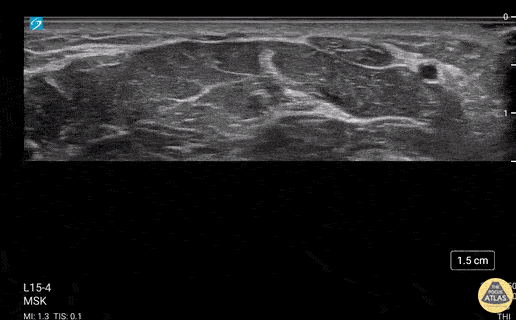

30 year old female with incidental finding of bifid median nerve. Video shows scanning proximal to distally in the volar forearm starting at distal third of the forearm and ending in the carpal tunnel. In the distal third of the forearm the median nerve can be seen as one bundle and hyperechoic compared to the surrounding muscles and displays typical "honeycomb" echosignature (hyperechoic perineurium surrounding hypoechoic endoneurium/axons). At the carpal tunnel, the median nerve can be seen as relatively hypoechoic compared to the surrounding hyperechoic tendons. Flexor retinaculum visualized as hyperechoic band immediately superficial to the median nerve in the carpal tunnel. Eben Alexander, DO Devesh Patel, MD Eastern Virginia Medical School